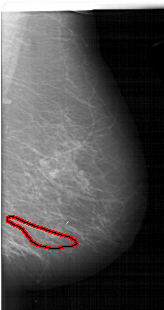

FILE: A_1129_1.RIGHT_MLO.OVERLAY

TOTAL_ABNORMALITIES 1

ABNORMALITY 1

LESION_TYPE CALCIFICATION TYPE PLEOMORPHIC DISTRIBUTION SEGMENTAL

ASSESSMENT 4

SUBTLETY 2

PATHOLOGY MALIGNANT

TOTAL_OUTLINES 1

BOUNDARY